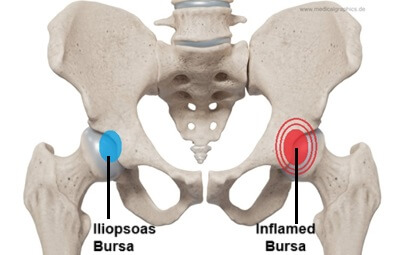

بورسیت لگن، شرایط رایجی است که بخش بیرونی کنار لگن و ران را در بالا تحت تاثیر قرار میدهد اما میتواند همچنین در ناحیه کشاله ران نیز احساس شود. بورسیت لگن، با التهاب بورس که یک کیسه ژله مانند قرار گرفته در لگن و همچنین در کل بدن است، ایجاد میشود.

این آسیب در بین دوندهها رایج است چون بر اثر استفاده بیش از حد و فشار تکراری ایجاد میشود. بورسها ماند ضربهگیر عمل میکنند تا اصطکاک بین استخوان و بافت نرم را کاهش دهند اما وقتی تحریک شده و ملتهب میشوند، باعث درد در آن نواحی خواهند شد.

دو نوع بورس بزرگ در لگن وجود دارد که بیشتر مستعد بورسیت هستند. دوندهها معمولاً در بخش بیرونی استخوان لگن (تروکانتر بزرگ) درد را احساس میکنند و التهاب این بورس، بورسیت تروکانتریک نامیده میشود.

بورسیت کمتر رایج، التهاب بورس تهیگاهی مازویی قرار گرفته داخل لگن (بخش کناری کشاله ران) است. اگرچه این شرایطی در مقایسه با بورسیت تروکانتریک، کمتر رایج است، اما به همان شیوه درمان میشود.